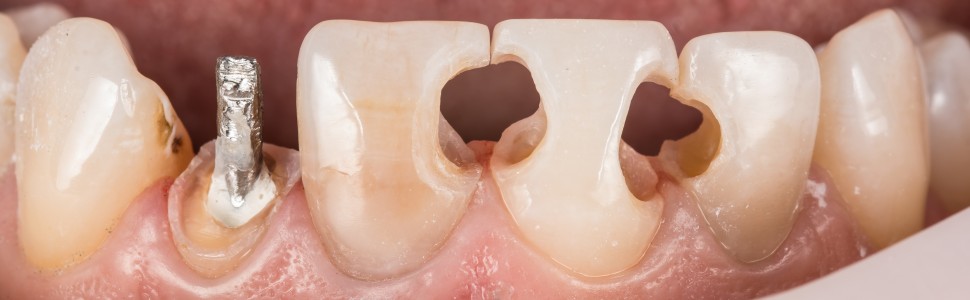

Przebarwienia wewnątrzpochodne stanowią wyzwanie w odbudowach estetycznych w odcinku przednim, wymagającym analizy wielu czynników przyczynowych, oceny możliwości rekonstrukcyjnych, także estetyki tkanek miękkich, w tym pozycji warg w kontekście uśmiechu dziąsłowego i występującego często sinego przebarwienia zenitu dziąsłowego. Konieczna jest także właściwa diagnostyka radiologiczna celem oceny stanu tkanek twardych zęba, poprawności i szczelności przeprowadzonego, z reguły lata wcześniej, leczenia endodontycznego, a co za tym idzie poprawnego opracowania części komorowej i kondycji tkanek okołowierzchołkowych.

Kolejne problemy, na jakie możemy trafić przy planowaniu leczenia odtwórczego, to stopień przebarwienia zębiny zęba, ocena możliwości wybielenia wewnętrznego, bez nadmiernego zwiększania ryzyka powstania resorpcji przyszyjkowej, wybór techniki – pośredniej lub bezpośredniej estetycznej odbudowy zębów, oraz materiału, a finalnie – szczegółowa analiza koloru i fotodynamiki materiału, zwłaszcza w kontekście prac asymetrycznych.